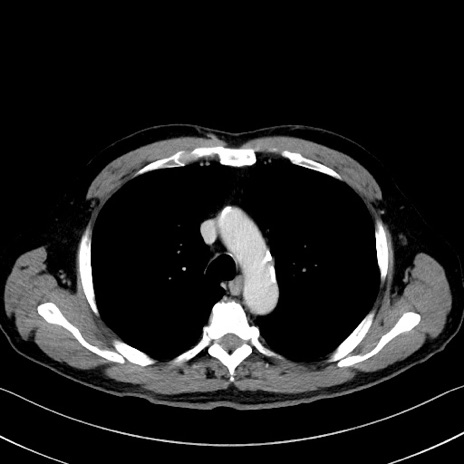

症例35(横断像)

【症例】70歳代 男性

【主訴】腹部膨満、嘔吐

【現病歴】昨日より腹部膨満感出現。本日増悪し、仙痛出現。嘔吐あり、受診。

【既往歴】糖尿病、胆摘後

【身体所見】BP 149/80mmHg、HR 74/min、BT 35.9℃、腹部:膨満、軟、圧痛なし。腸雑音減弱あり。上腹部正中切開瘢痕あり。

【データ】WBC 13500、CRP 1.72